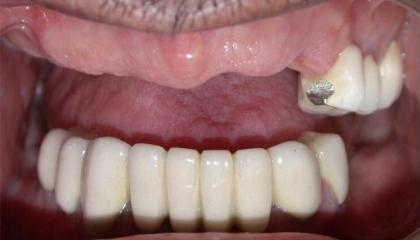

After